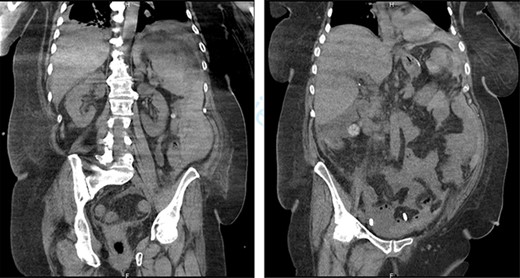

Abdominal CT showed signs of non-complicated appendicitis: intra-appendicular liquid, microstercoliths and peri-appendicular inflammation (Fig. 1).

Emergency CT: acute appendicitis with: intra-appendicular liquid, microstercoliths and peri-appendicular inflammation.